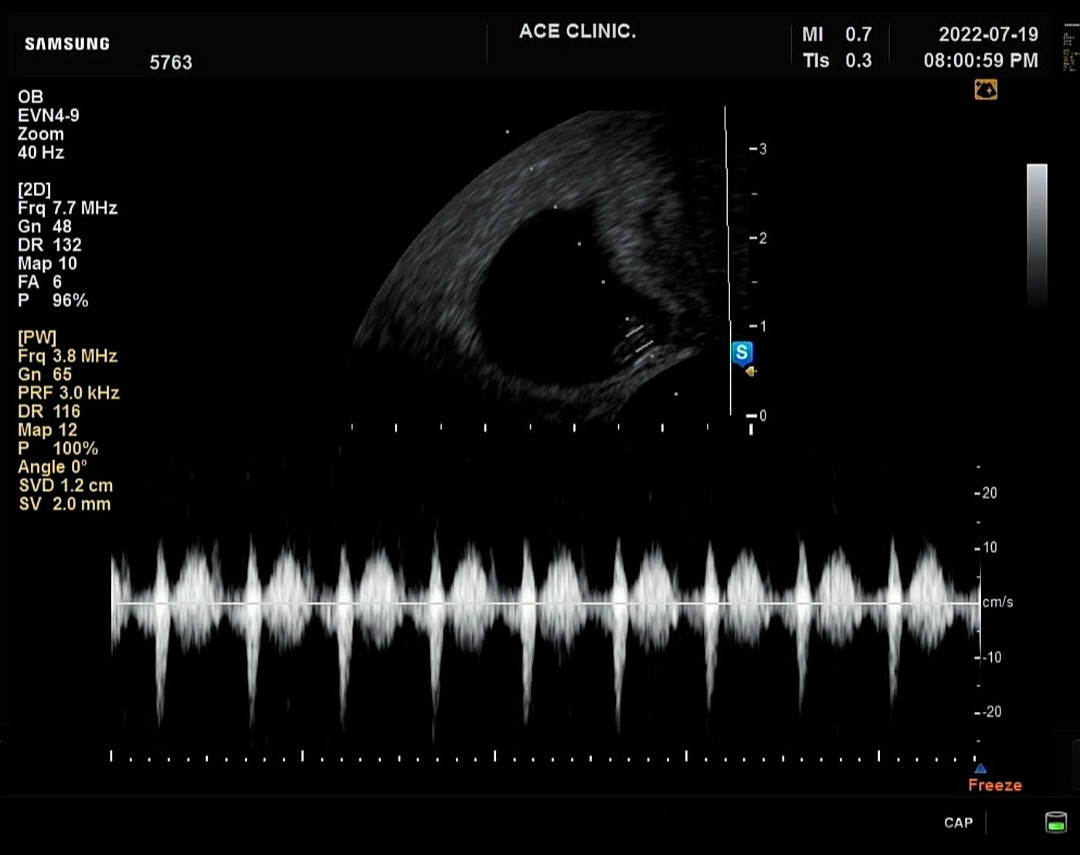

우리 살구 심장은 아주 빨리 뛰었어. (의사 선생님 말씀이, 엄마 뱃속에 있는 아이 심장은 어른들보다 훨씬 빨리 뛰어야 하고 그래야 건강한거라고 하셨어) 그렇게 작은 심장이, 그렇게 믿을 수 없을 정도로 빨리 뛸수 있다는 걸 아빠는 몰랐어. 그리고 그 심장이 절대 멈추지 않게, 적어도 앞으로 100년 정도는 멈추지 않고 잘 뛸수 있도록 아빠와 엄마가 함께 지켜내야만 한다는 것도, 미처 생각해 본 적 없는 일이었지. 너무 소중해서 동시에 너무 불안하기도 한 그런 감정이었던 것 같아. 내가 잘 할수있을까? 하는 두려움. 그리고 살구의 심장이 뛰는 동안 얼마나 많은 일들이 있을까. 그중엔 어렵고 힘든 일도, 슬픈 일도 있을 텐데, 우리 살구 심장이 잘 버텨내겠지? 하는 바보 같은 생각도 들었어.